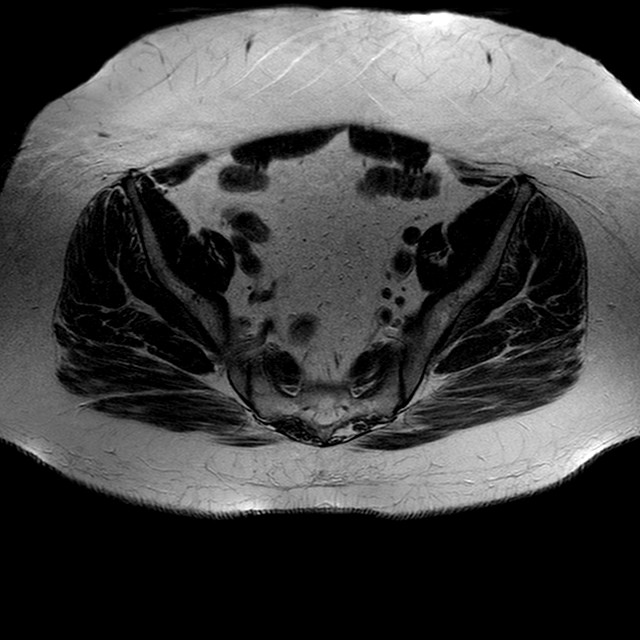

Esami: RMN BACINO

T2w TSE

Evidenti e simmetriche alterazioni osteofitosiche in regione coxo femorale con riduzione delle rime articolari. Degenerazione completa del cercine glenoideo. Non attuali segni di versamento articolare. Non segni di edema osseo che escludono attuale algodistrofia od osteonecrosi. Lieve e simmetrica riduzione del trofismo della muscolatura glutea.